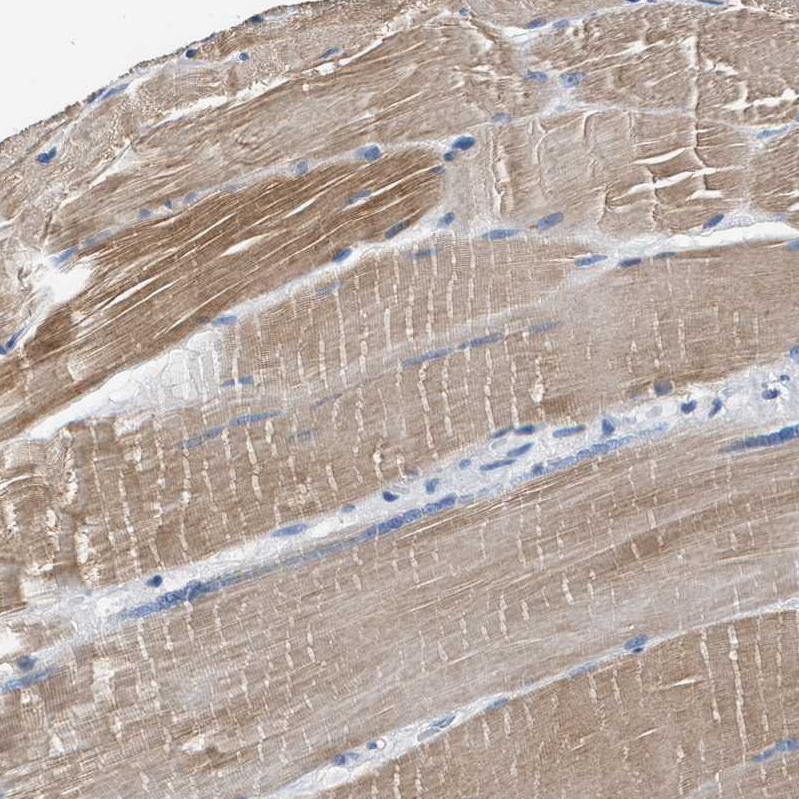

Immunohistochemical staining of human skeletal muscle shows moderate to strong cytoplasmic positivity in myocytes.